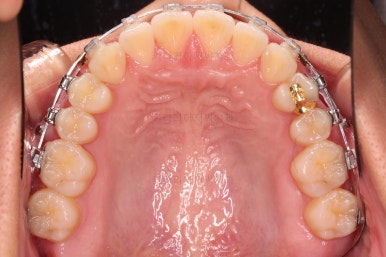

윗니의 배열과 위치는 거의 완성이 되었고요.

아래는 아직 틈이 많이 보이죠.

어금니를 부산치아교정 통해 계속 앞으로 당겨줍니다.

우선 가지런하게 하는 작업을 했고요.

교합을 맞춰야 하기 때문에 윗니는 통째로 약간 뒤로 밀어줍니다.